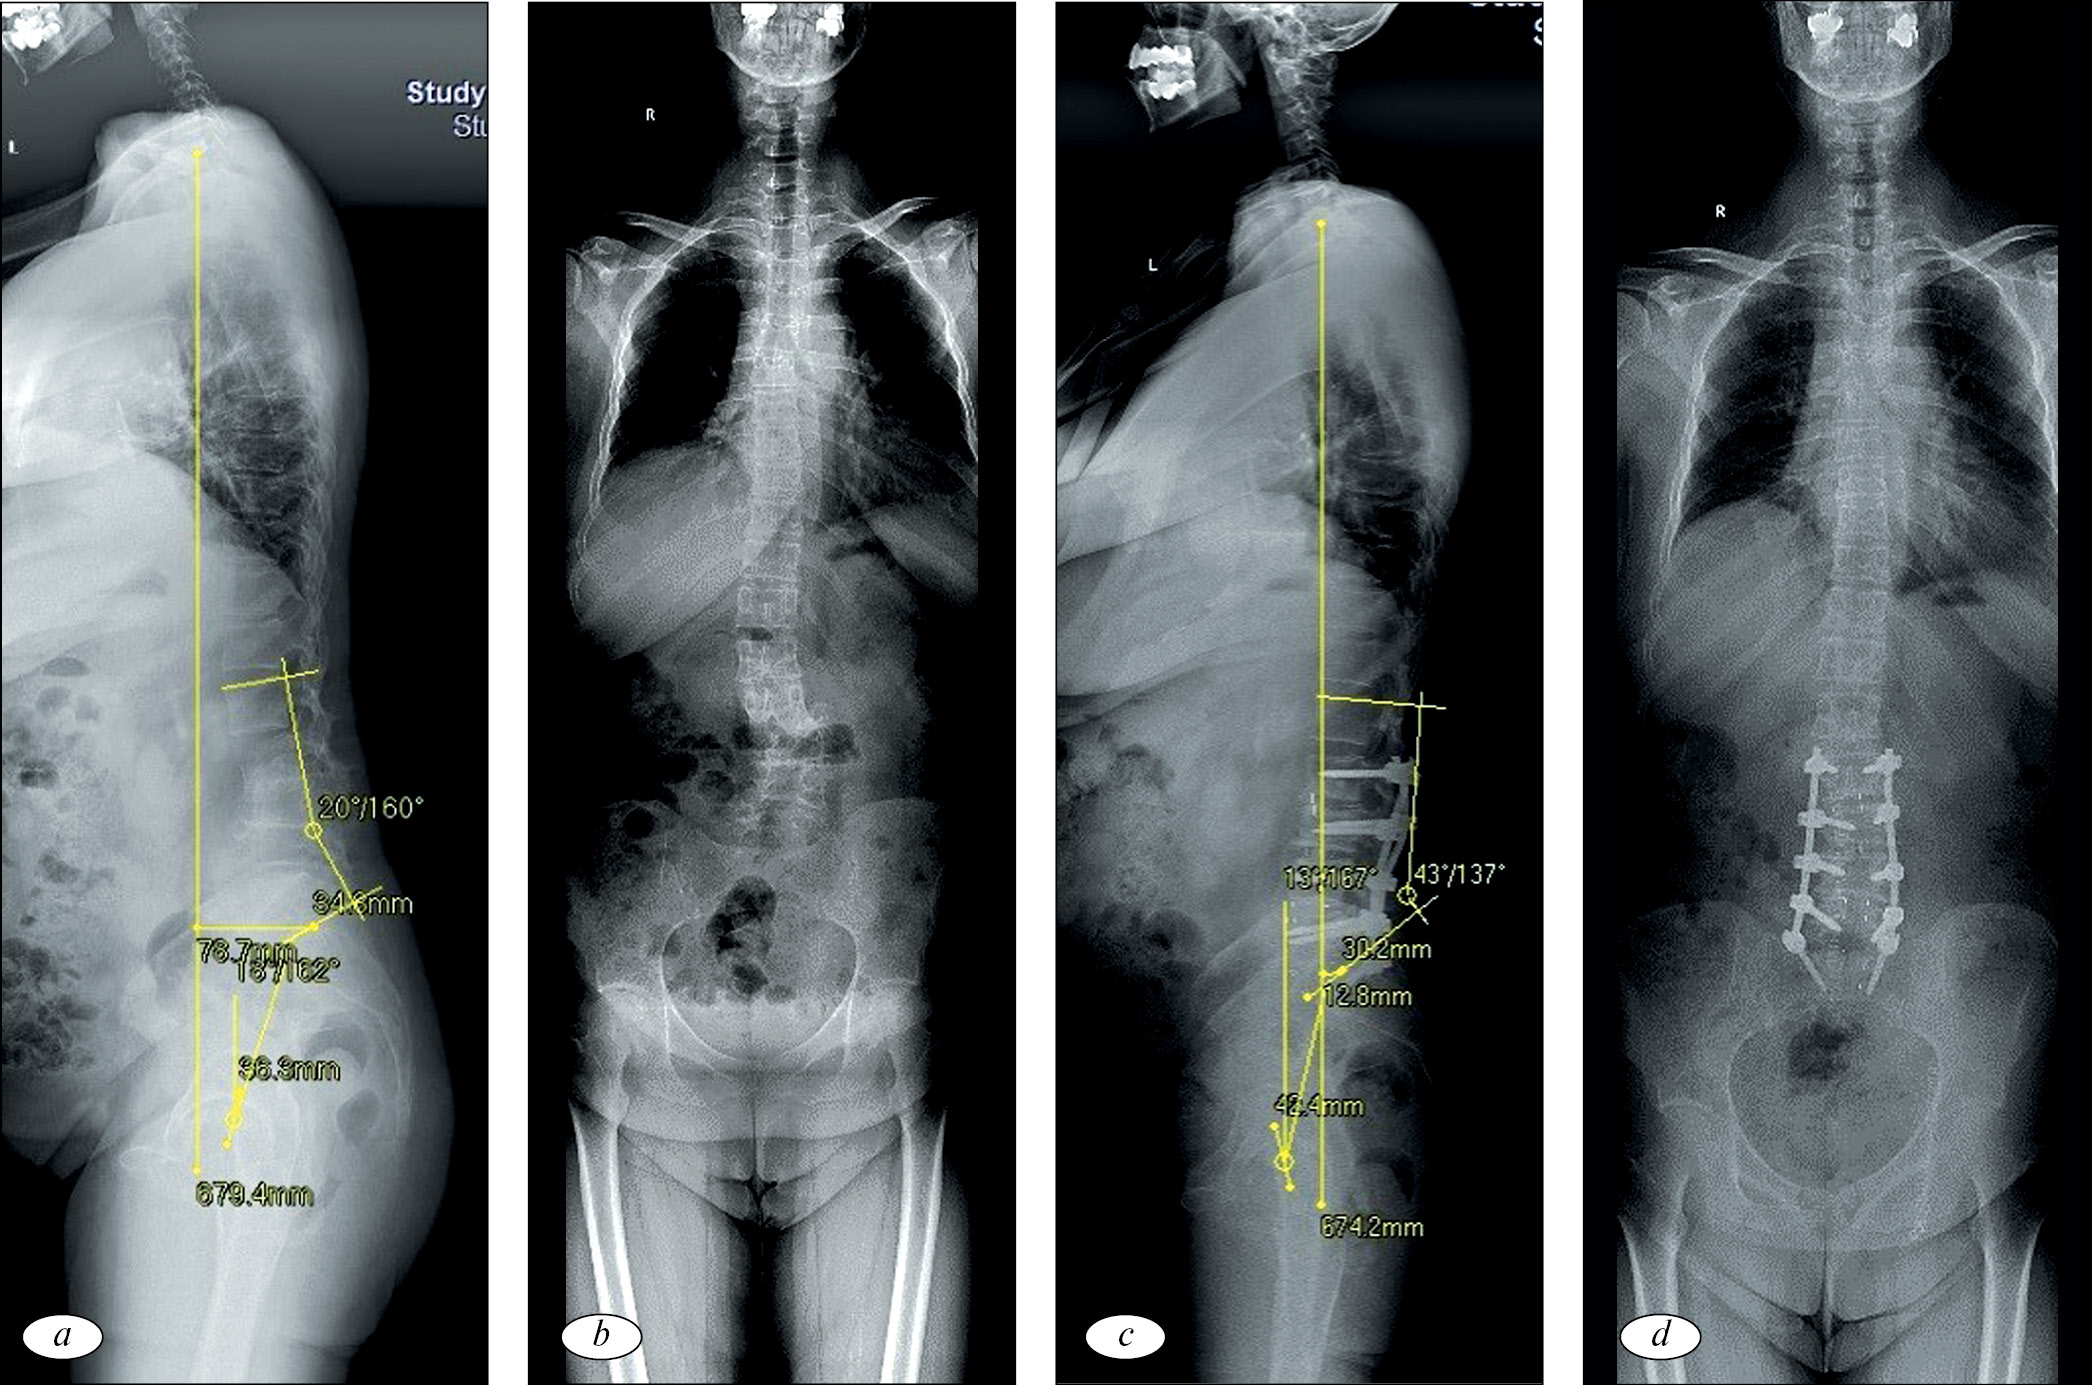

На рис. 1 и 2 представлены клинические примеры хирургического лечения пациентов из группы PSO и комбинированного лечения.

Рис. 1. Рентгенограммы пациентки, 55 лет, с дегенеративным стенозом и нарушением сагиттального баланса, проявляющихся выраженным болевым синдромом в поясничном отделе позвоночника, синдромом компрессии L4, L5 корешков слева: а и b — дооперационные рентгенограммы в степ-режиме в боковой и прямой проекциях. PI — 57°, PI-LL — 54°, PT — 35°, SVA — 109 мм, LDI — 33 %, GAP — 11 баллов, III тип Russouly. Пациентке проведено: PSO L3, PLIF на уровне L4-L5, остеотомия Schwab II типа на уровне L4-L5, задняя винтовая фиксация L1-S1; с и d (через 1 год) — рентгенограммы в степ-режиме в боковой и прямой проекциях. PI — 57 °, PI-LL — 5°, PT — 18°, SVA — 38 мм, LDI — 25 %, GAP — 4 балла